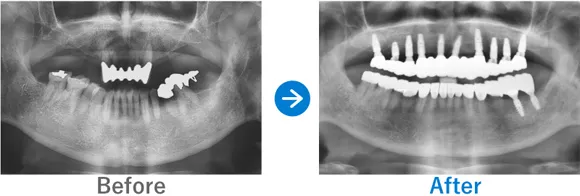

歯が1本もない状態からインプラント治療で噛める幸せを取り戻された方

歯が1本もない状態、10年以上前から上下総義歯(総入れ歯)

上顎ALLON6、下顎ALLON4、

リオペ上顎追加埋入ザイゴマインプラント2本

9,823,000円(上顎6,248,000円、下顎3,575,000円/内訳:上顎オールオン6(ノーベルザイゴマインプラント2本・ストローマンインプラント4本)、下顎オールオン4(ストローマンインプラント4本)3Dモデルガイド*、仮歯、セデーション、ボツリヌストキシン注射、3D模型、保証10年)

来院の背景

10年以上前から上下義歯(総入れ歯)だが、義歯が痛くて、食事に困っている。他院にて仮義歯を作ってもらっていたが担当医が辞めたこともあり、インプラントを検討。ネットで探して退院。痛みなく食事がしたい。

治療結果

上下ALLON4、右上5、左上3、リオペザイゴマインプラント2本追加順調の経過、治療終了、メンテナンス来院。インプラントで噛めるようになり、喜んでいただいた。しっかりセルフケアを頑張っておられます。お顔の表情も明るくなられて、気持ちも前向きに過ごされています。